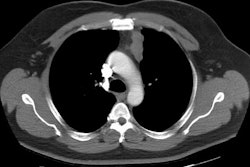

Middle mediastinal masses:

1- Adenopathy, aneurysms, forgut duplication cysts, hiatal hernia, and tracheal lesions